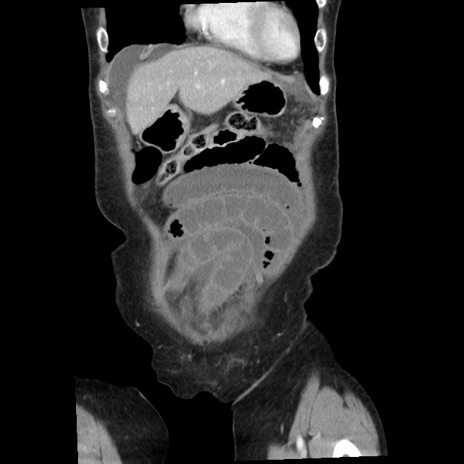

症例1(冠状断像)

【症例】80歳代女性

【主訴】腹痛

【現病歴】8時間前から腹痛あり来院。

【既往歴】糖尿病、脂質異常症、子宮体癌にて子宮全摘術

【身体所見】意識清明・会話良好だが腹痛で苦悶様、全腹部にわたって反跳痛と圧痛あり

【データ】WBC 13600、CRP 0.14、LDH 224、CK 90